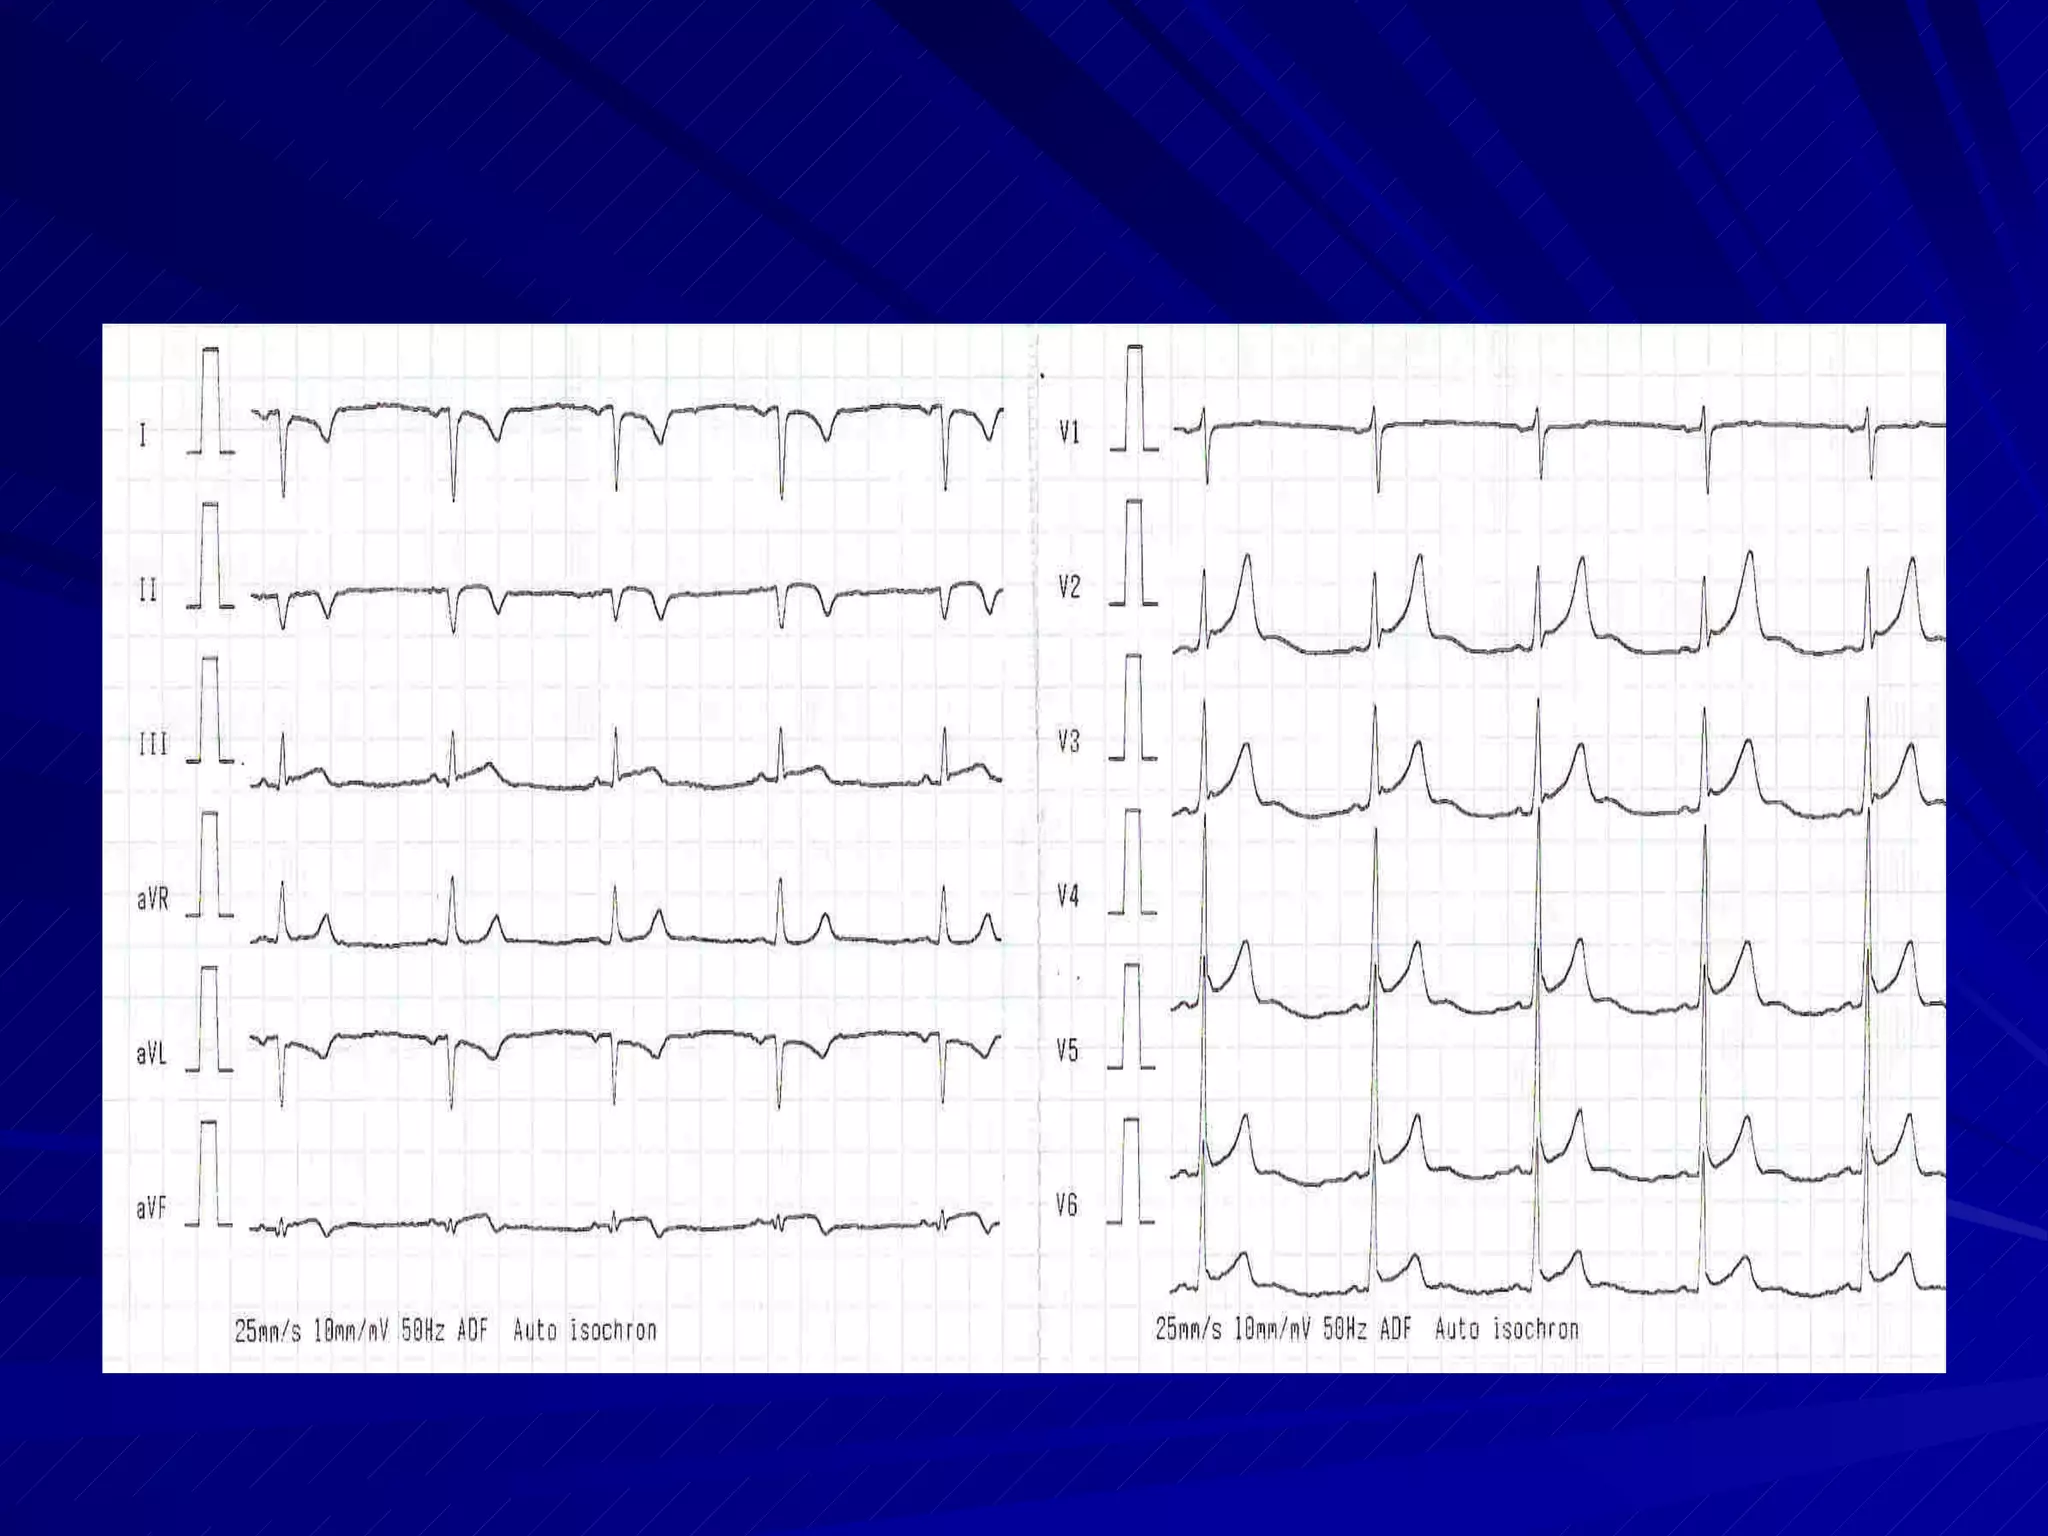

Basics ECG graphs: 1 mm squares 5 mm squares  Paper Speed: 25 mm/sec standard Voltage Calibration:  10 mm/mV standard

Normal Sinus Rhythm Originates in the sinus node Rate between 60 and 100 beats per min P wave axis of +45 to +65 degrees, ie. Tallest p waves in Lead II Monomorphic P waves Normal PR interval of 120 to 200 msec Normal relationship between P and QRS Some sinus arrhythmia is normal

Normal QRS complex Completely negative in lead aVR , maximum positivity in lead II rS in right oriented leads and qR in left oriented leads (septal vector) Transition zone commonly in V3-V4 RV5 > RV6 normally Normal duration 50-110 msec, not more than 120 msec Physiological q wave not > 0.03 sec

Features of  ERPS Vagotonia / athletes’ heart Prominent J point Concave upwards, minimally elevated ST segments Tall symmetrical T waves Prominent q waves in left leads Tall R waves in left oriented leads Prominent u waves Rapid precordial transition Sinus bradycardia E arly  R ecognition  P revents  S treptokinase infusion !